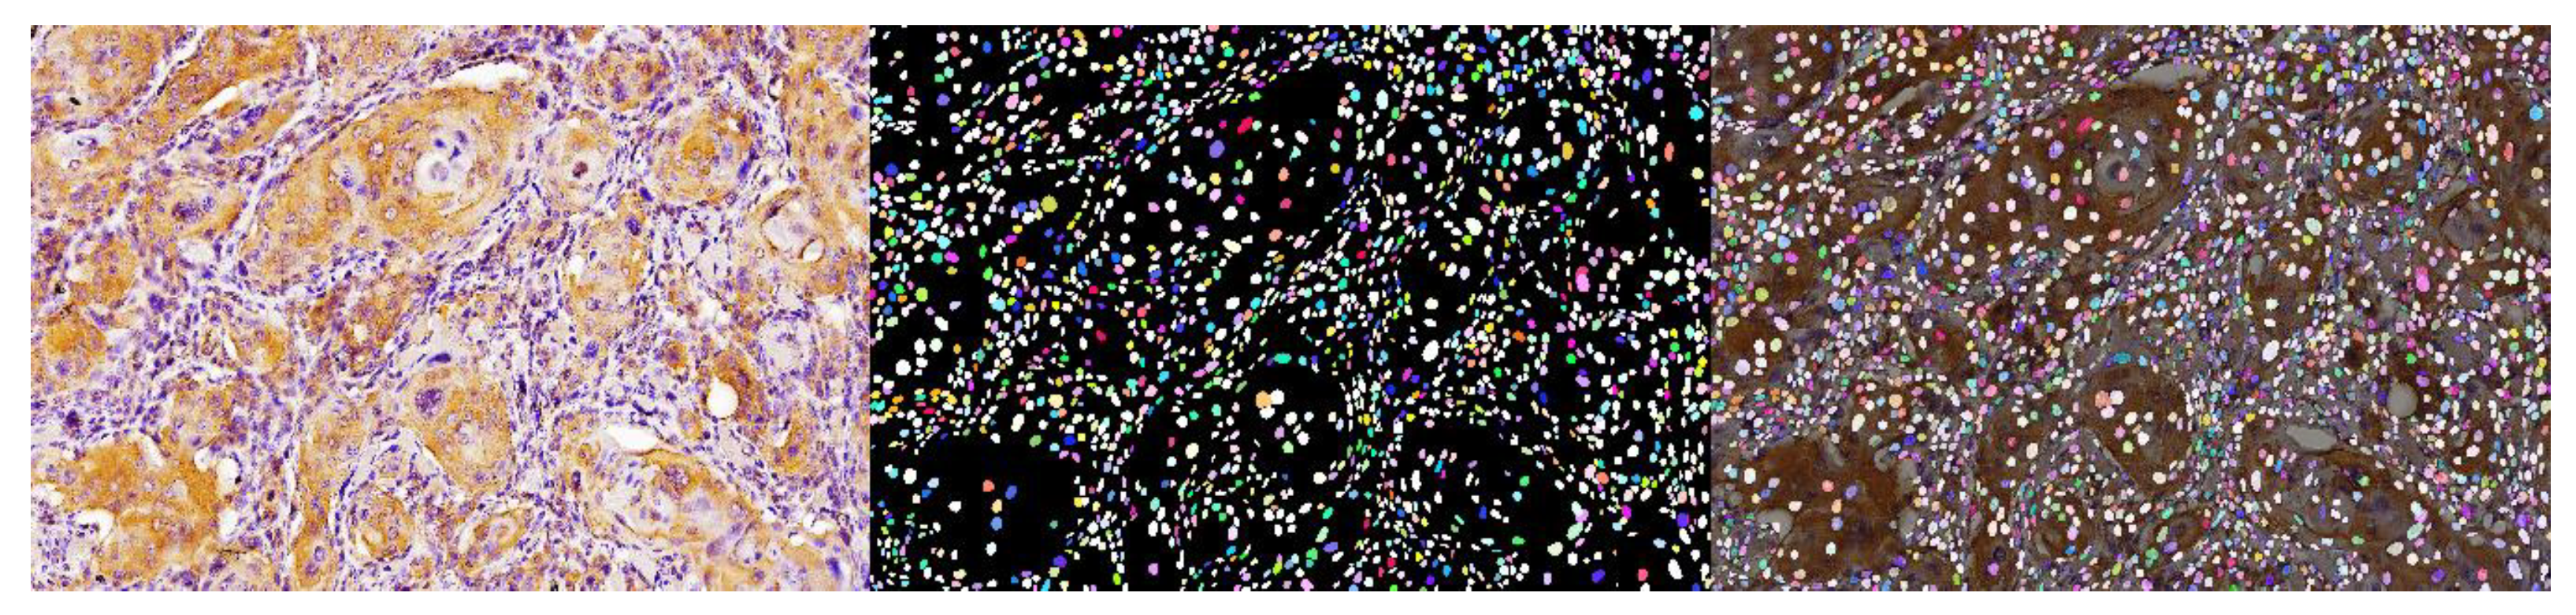

9. Role of AI in Immunofluorescence and Immunohistochemistry Oral Cancer Images

- Prado, V.P.; Landini, G.; Taylor, A.M.; Vargas, P.; Molina, R.B. Spatial distribution of CD34 protein in primordial odontogenic tumour, ameloblastic fibroma and the tooth germ. J. Oral Pathol. Med. 2022, 52, 181–187. [Google Scholar] [CrossRef] [PubMed]

- Schmidt, U.; Weigert, M.; Broaddus, C.; Myers, G. Cell detection with star-convex polygons. In Proceedings of the International Conference on Medical Image Computing and Computer-Assisted Intervention, Granada, Spain, 16–20 September 2018. [Google Scholar]

- Puladi, B.; Ooms, M.; Kintsler, S.; Houschyar, K.S.; Steib, F.; Modabber, A.; Hölzle, F.; Knüchel-Clarke, R.; Braunschweig, T. Automated PD-L1 Scoring Using Artificial Intelligence in Head and Neck Squamous Cell Carcinoma. Cancers 2021, 13, 4409. [Google Scholar] [CrossRef] [PubMed]

| Vahadane A et al., 2023 [49] Puladi B et al., 2021 [50] | Obtain reproducible and reliable scores of immunofluorescence imaging of PD-L1 | WSI. DL and ML. QuPath. Matlab. | 54 HNSCC | 97.2% |

| Tsakiroglou et al., 2020 [51] | Quantify the frequencies of cell–cell spatial interactions occurring in the PD1/PD-L1 pathway | WSI. DL and CNN. QuPath. | 72 OPSCC | 88.3% |